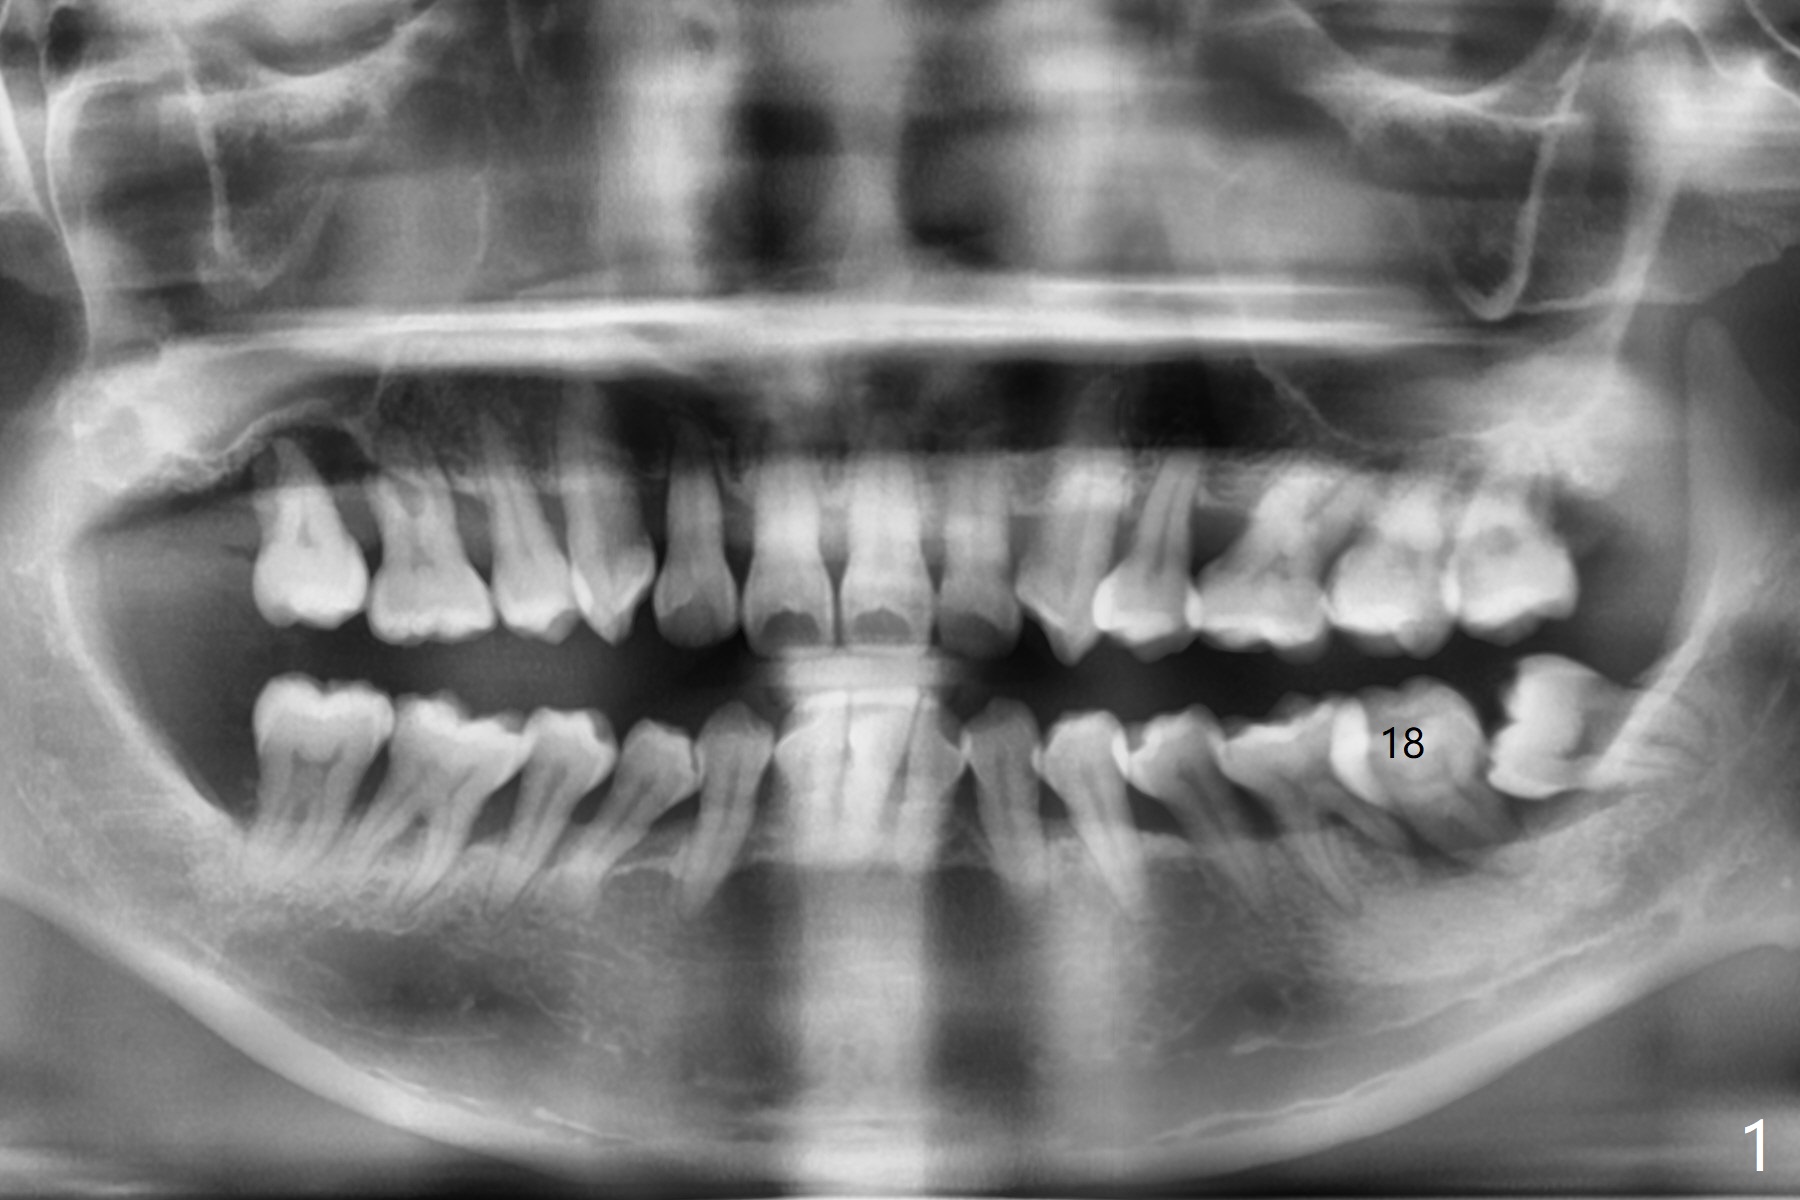

A 44-year-old woman has severe chronic periodontitis. The tooth #18 is nonsalvageable (Fig.1). To avoid distal end guide, do not remove the 3rd molar in the lab. While a 5x7.3 mm implant is long for the site (Fig.2), a 5.5x5.5 mm one seems to be a better option (Fig.3). The latter could be 1 mm more coronal. The last drill (5.0 mm) and cortical tap will be used free hand. #17 will be extracted after implantation. Since the patient is reluctant to have #16 to be extracted, place #18 implant ~ 1-2 mm more distal so that the implant crown will have some occlusal contact with #16. Prepare IS extra wide kit. Or use a 8/7 mm trephine bur to harvest cortical bone from the ramus. Drill a hole for fixation screw before removing the onlay graft. Keep the 3rd molar if possible. Prepare Tatum spacers to measure the size of #18 socket opening. In fact, the lab is able to place a 5x7.3 mm implant with 2 thread exposure buccal. Prepare sticky bone and PRFx2 to prevent periimplantitis. Soak one O-ring in case of having to extend osteotomy by .5 mm (next longer drill (1.5 mm) - 1 mm (O-ring)). For socket shield at #18 (Fig.6 *), section the tooth horizontal with a new surgical fissure bur (Fig.4 black area), use an end-cutting bur to remove buccal edge of the root (Fig.5 red area) and finally remove the lingual portion of the root (Fig.6 pink). Insert 4.5x10 mm dummy implant to determine whether the final implant 5x7.3 mm (bottom of the 1st line) will probably contact the shield. Buccal view of the lingually inclined 2nd molar (Fig.7). After removal of the crown of the 2nd molar (Fig.8 occlusal view), the lingual portion of the root is resected (Fig.9 black area). CT coronal sections show socket shield formation (Fig.10,11).